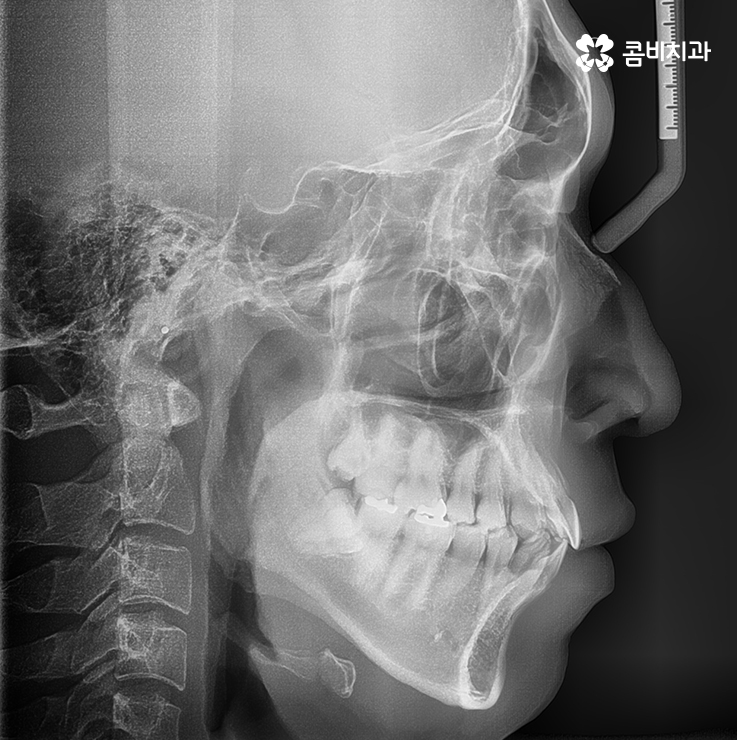

교정 장치를 선택하기 전에 골격 상태와 치열, 얼굴형 등을 먼저 정밀 검진해야 합니다.

위 사례의 경우 앞니만 치아부분교정 통해서 치료가

이뤄진 사례로 치아의 돌출 여부나 골격, 교합 등을

고려하여 큰 문제 없이 치료가 가능했던 사례입니다.

위 사례의 경우 유독 앞니 위주로 치아가 벌어져 있는 상태이며

옆모습의 경우에도 비교적 양호한 상태입니다.